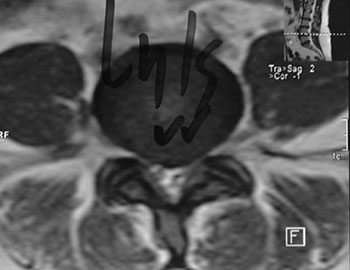

Foram realizadas radiografias onde, não sendo encontradas alterações significativas (Fig. 6); optado então por realizar ressonânca magnético sendo evidenciada uma hernia contida L4-L5 (Fig. 7).

Fig. 7a

Fig. 7b